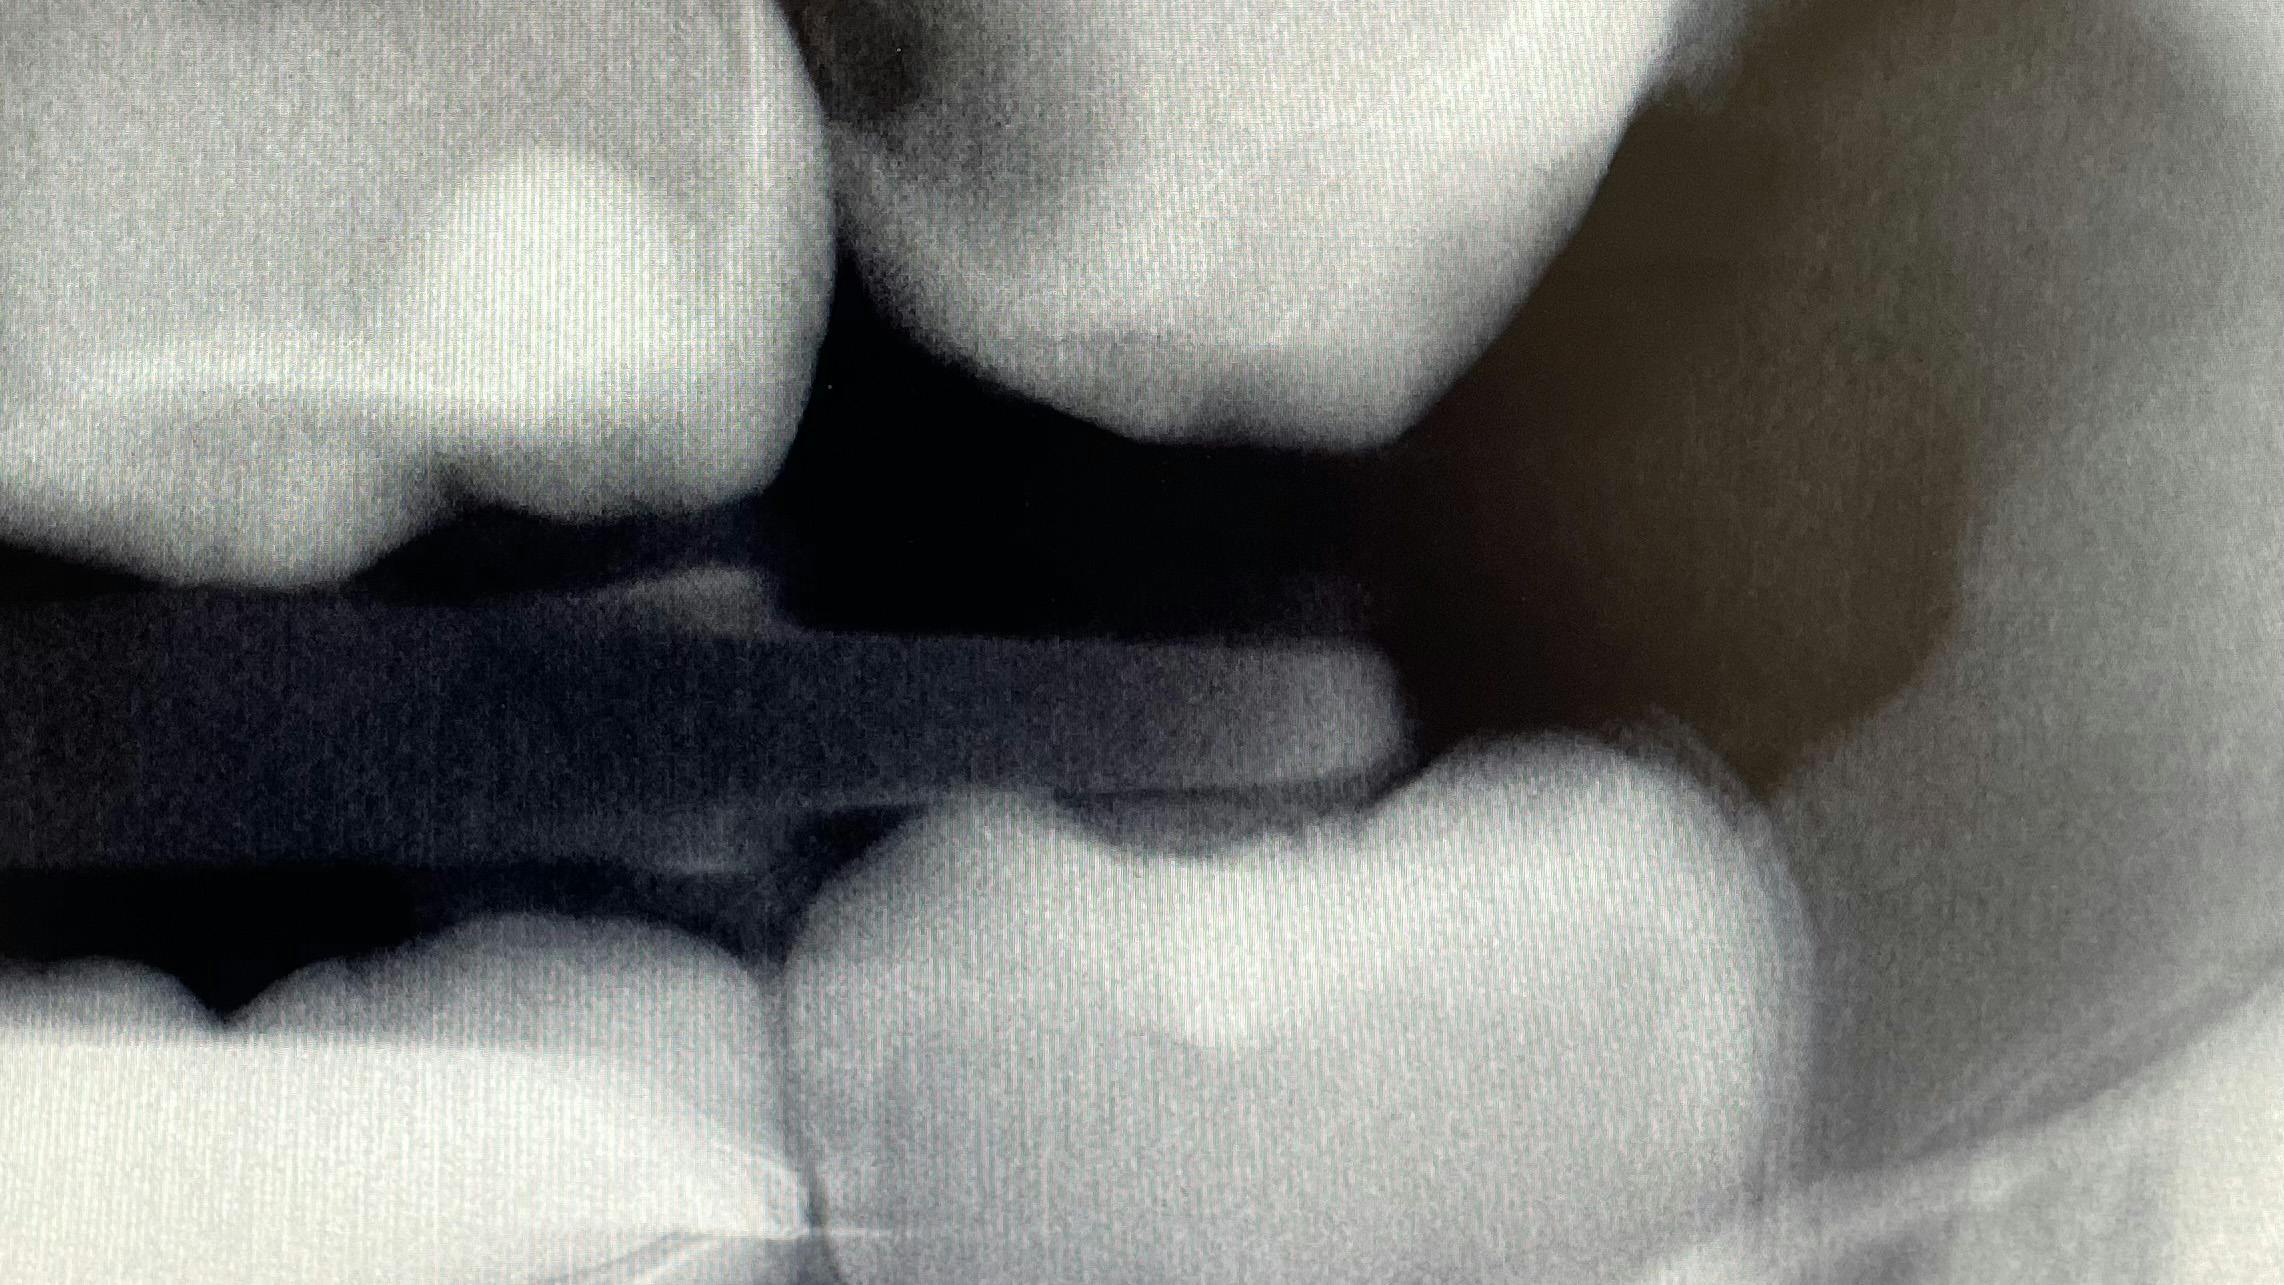

What’s unique about this system is that it uses nanotube technology to capture standard 2D images (figure 2) and gives you the option of taking a tomosynthesis image, which captures multiple images from several angles (figure 3). Images are compiled into a sliced volume and dissected into 0.5 mm or 0.1 mm slices that you can scroll through, rotate, enlarge, measure, and adjust. The system can “un-overlap” many teeth; this is convenient because with regular 2D x-rays, I had to retake the image at different angles and often with little success.

I see more complications and pathologies when using 3D tomosynthesis than I ever did with my old 2D images (figure 4). I can treat more because I can see more bone loss, interproximal caries, fractures, resorptions, abscesses, and more (figure 5).

In fact, twice today I was able to see something with Portray that wasn’t visible in the original 2D x-ray (figure 6). I don’t always take 2D images now, but I do when I think the case is straightforward or the patient has very little dental history. I often end up taking a tomosynthesis image just to be safe. With the 3D image I can scroll from buccal to lingual through the tooth and get much more data (figure 7). The new system has replaced my 2D PAs and bitewings.

Fortunately, 3D intraoral tomosynthesis found its way into the dental field. Based on the findings from a study out of the University of North Carolina, dentists who use 3D tomosynthesis for intraoral x-rays can detect approximately 36% more caries (figures 8 and 9).1 That’s tremendous!